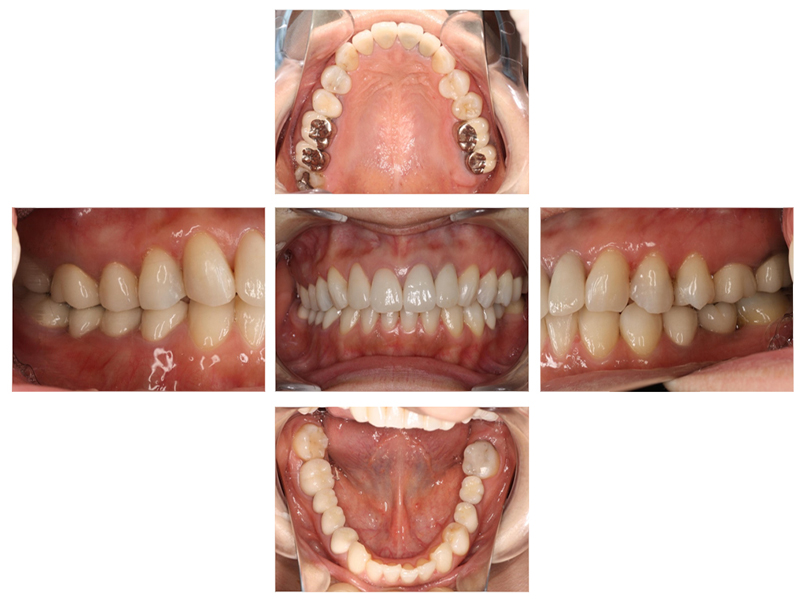

▼ ケース5 下顎前歯部叢生症例

初診時口腔内写真

初診時X線写真

治療終了時

before

after